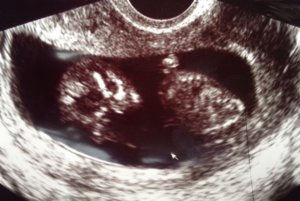

Bent a vizsgálaton ismét félve ültem a székbe, de szerencsére ismét minden a legnagyobb rendben volt. Az orvos megerősítette, hogy mindene megvan, látta (és mi is) a kezeit, lábait, a gyomrát, a tüdejét, a szívét, a bordáit, a hibátlan gerincoszlopát, a koponyáját. Mint valami biológiaóra, olyan volt. 🙂 Sőt, az orvos a nemét is 80%-ra biztosra mondta (de még nem árulom el). A méretei a korának megfelelőek voltak, Down-szindróma gyanúja nem merült fel.

A legnagyobb élmény pedig az volt, hogy MOZGOTT! 🙂 Ott ficánkolt, integetett, hajlítgatta a lábát, mindezt bennem, és én ebből semmit nem éreztem! Nagyon furcsa volt, hogy ezt csinálja már hetek óta, és most már a születéséig folyamatosan mocorogni fog odabent.

Ismét kaptunk képeket, egy kis alien nézett vissza ránk a fotóról. Íme: